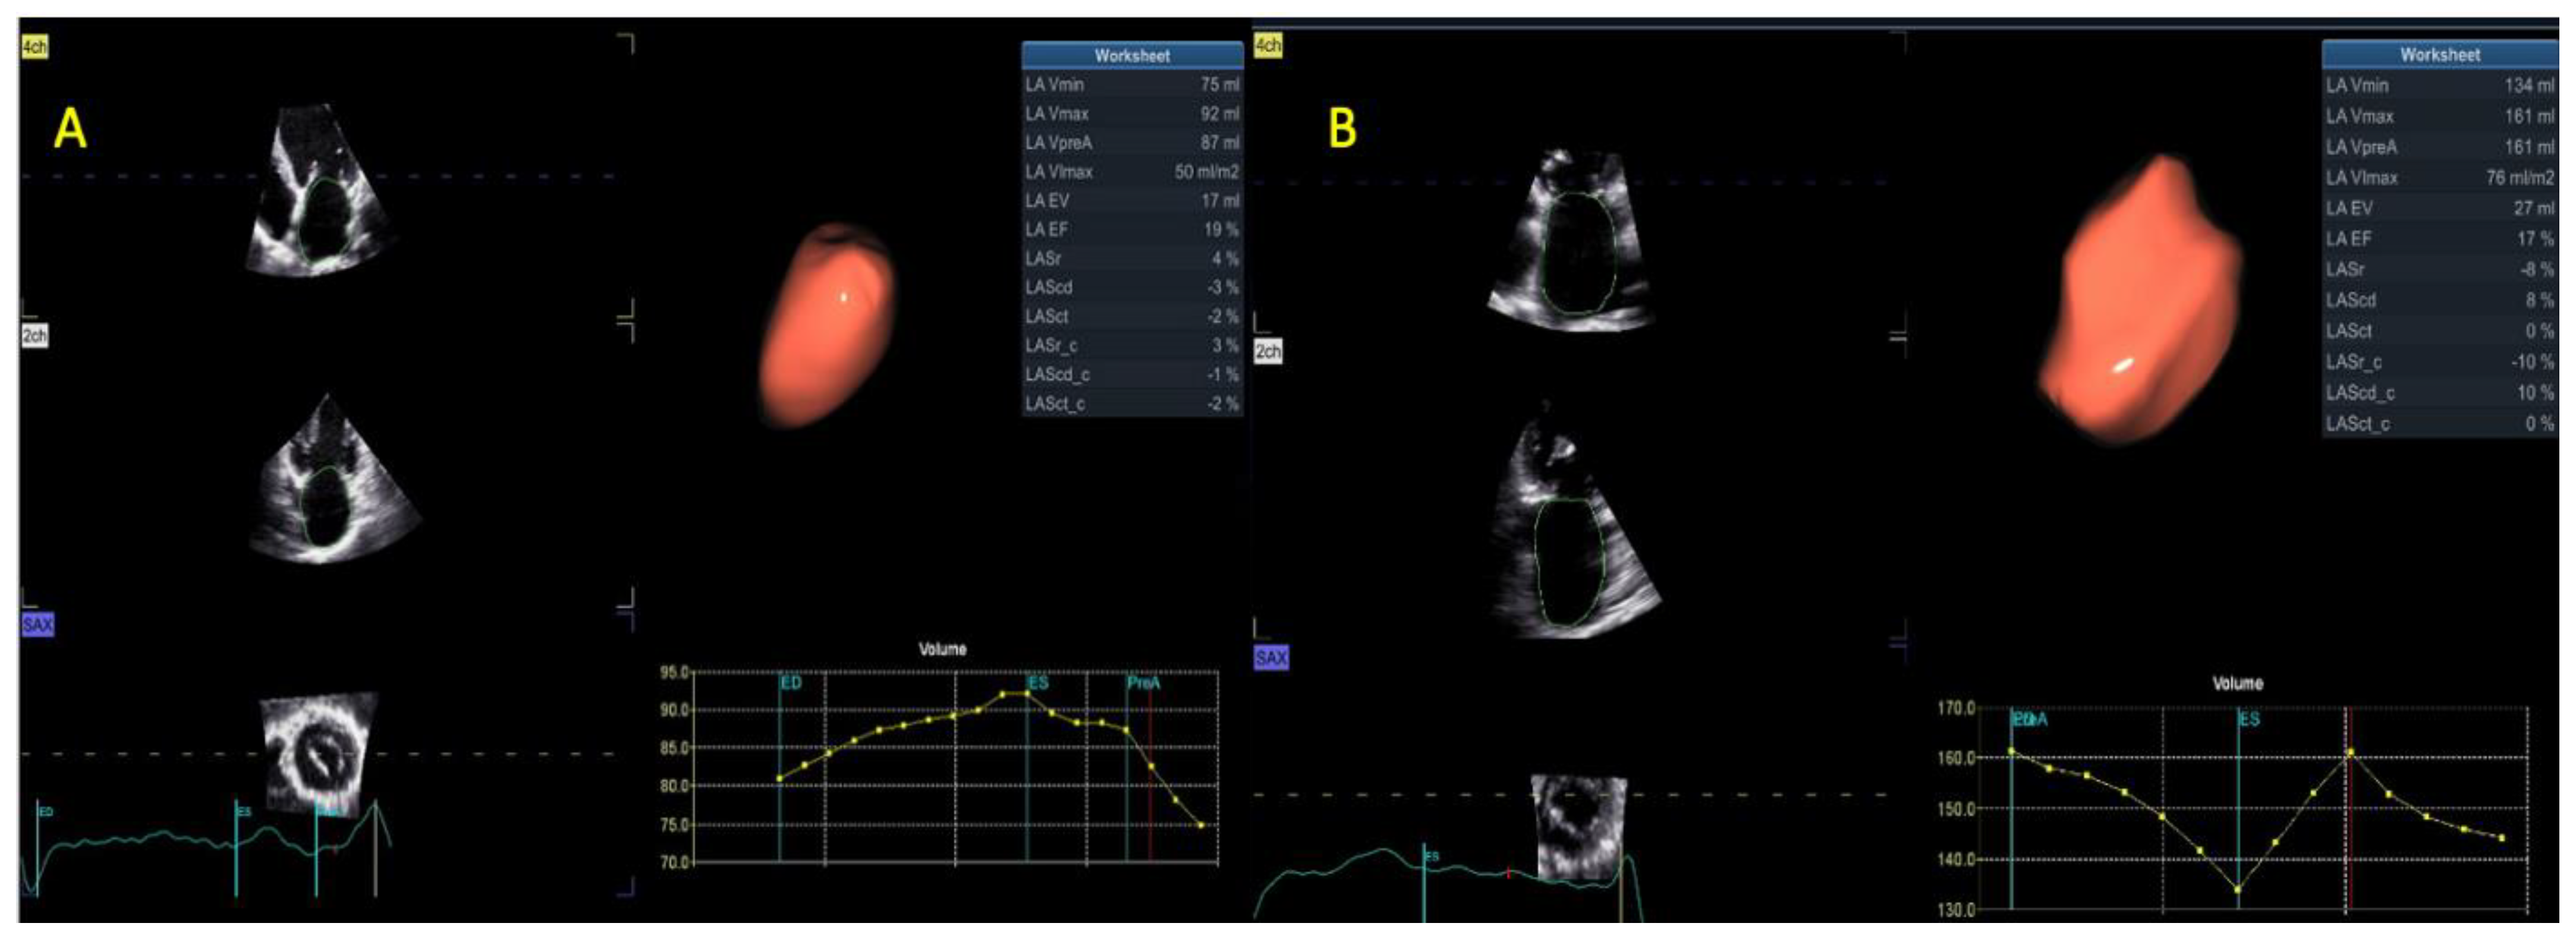

| 3D LAV max (mL) | 80 ± 22 | 107 ± 35 | <0.001 |

| 3D LAV max index (mL/m2) | 44 ± 13 | 55 ± 14 | 0.002 |

| 3D LAV min (mL) | 58 ± 25 | 89 ± 29 | <0.001 |

| 3D LAV min index (mL/m3) | 32 ± 14 | 44 ± 15 | 0.002 |

| 3D LA EF (%) | 30 ± 15 | 17 ± 6 | <0.001 |